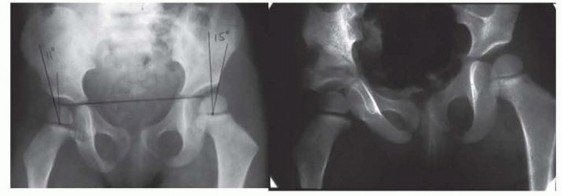

Before lengthening, hip stability should be determined radiographically. The best indicator is the CE angle. If the CE angle is less than 20 degrees, a Dega osteotomy should be performed before lengthening. In addition, the AI should be less than 30 degrees. If the CE angle is borderline 20 degrees but the AI or inclination of the sourcil is high, it is better to err on the side of caution and perform a Dega osteotomy ( FIG 6 ).

Coxa vara should be corrected before lengthening if the neck-shaft angle is less than 120 degrees. When coxa vara and hip dysplasia are present and when the coxa vara is severe, the superhip procedure is performed. The pelvic and femoral osteotomies should be performed 12 months before the first lengthening. The superhip procedure is a